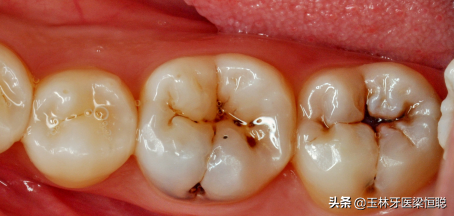

很多患者由于早期沒(méi)有對(duì)蛀牙采取調(diào)節(jié),導(dǎo)致牙齒上有蟲(chóng)洞。牙齒有蛀牙補(bǔ)個(gè)牙齒需要多少錢?成為一個(gè)熱門的問(wèn)題。由于很多人都有這樣的困擾,所以這次專門來(lái)解答牙齒有蛀牙補(bǔ)個(gè)牙齒需要多少錢?

蛀牙

牙齒有蛀牙補(bǔ)個(gè)牙齒需要多少錢?牙齒爛個(gè)洞都是由于蛀牙引起的,主要看蛀牙的嚴(yán)重程度決定,以下是一些不同程度的蛀牙。

1、在溫和的情況下,僅在牙釉質(zhì)或牙本質(zhì)層上發(fā)生腐爛時(shí),這是一種常見(jiàn)的牙科填充程序。該程序是指去除所有侵蝕的牙齒腐質(zhì)組織并為復(fù)合樹(shù)脂填充物備洞。先把蛀洞周圍已破壞的組織去除,再以適當(dāng)?shù)某涮畈牧线M(jìn)行填補(bǔ),進(jìn)而恢復(fù)牙齒表面的完整性,防止蛀牙的繼續(xù)進(jìn)行。這個(gè)時(shí)候補(bǔ)牙史便宜的。

淺齲初期